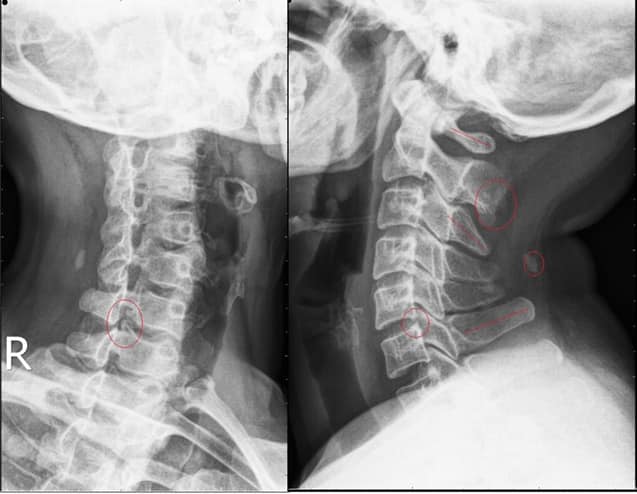

Cervical Spine Treatment Cases 頸椎治療案例 #疼痛三年頸椎病患者親手寫下治療紀錄 #交感神經型頸椎病 #症狀錯綜複雜 2020.10.02 #困擾四年多胸悶手麻頭暈醫案 #一切原因居然是頸椎出問題 #交感神經型頸椎病症狀錯綜... 2020.09.11 #交感神經型頸椎病引起的耳鳴 #耳鳴將近八個月終於得到重大改善 #曾經耳鳴到無法睡覺... 2020.08.22 #感謝板橋蘇先生熱情見證 #神經根型頸椎病卡壓 #曾痛痛到左手無法騎單車撥桿 #麻脹刺... 2020.08.04 #後縱韌帶鈣化引起椎管狹窄 #痛到完全無法睡覺長達半年以上 #原本已經準備開刀最後逆... 2020.07.16 #牽一頸而動全身的特殊醫案 #兩分鐘瞭解交感神經型頸椎病 #絕望的黑暗人生看到一絲希... 2020.07.03 #長達七年的頸椎疼痛是怎麼回事 #神經根型頸椎病 #低頭族跟家庭主婦辛苦了 #逆轉勝醫... 2020.07.01 #頸椎整合中醫微創療法 #感謝新竹黃大哥熱情見證 #逆轉勝成真醫案 2020.06.25 #頸椎病手術後也要要好好保健 #毛巾操很重要再度上場 #感謝某大醫學中心主任見證 2020.06.24 #這些症狀很可能都是頸椎出問題 #患者看七種不同科別醫師找不出原因 #交感神經型頸椎... 2020.06.09 #消失的頸椎曲線能夠回來嗎? #核磁共振前後對比椎管容積打開 #脊椎整合中醫微創療法❤... 2020.06.05 #感謝新竹薛大哥熱情見證 #頸椎整合中醫微創療法 治療:4/21~5/30(八次) 效果顯著... 2020.05.30 從宜蘭來的游小姐患者熱情見證 頸椎整合中醫微創療法 逆。轉。成。真。 2020.05.29 #脊髓型頸椎病案例 2020.05.26 #感謝新北市黃小姐熱情見證 #疼痛時間超過一年 #晨起麻痛到不行的日子長達半年以上 #... 2020.05.16 ← 上一頁 5 6 7 8 9 下一頁 →